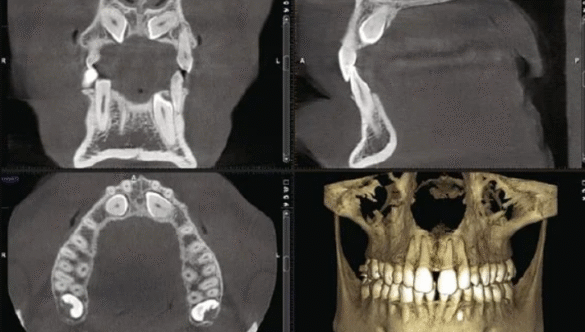

Advanced Dental Technology for Better Precision

Modern dentistry depends on precision, and advanced technology plays an essential role in delivering better outcomes.

At Nova Dental Hospital, our CBCT technology supports:

- Implant planning

- Root canal assessment

- Bone analysis

- Wisdom tooth diagnosis

- Jaw evaluation

- Complex restorative planning

This allows us to provide more informed treatment recommendations and better long-term support.